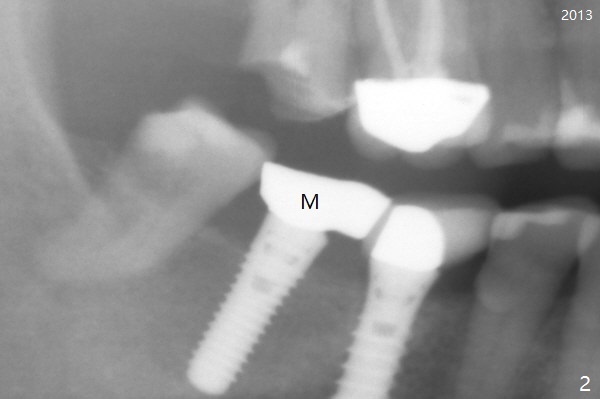

A 50-year-old woman is a bruxer. There are 3 PFM crowns at #3, 30 and 31 (Fig.1). A full metal crown is changed at #31 because of porcelain chip 3 years later (Fig.2). A Zirconium crown is fabricated at #2 after tooth fracture; porcelain chips at #30 and the PFM crown is removed (Fig.3) for Zirconium one (Fig.4). It appears that the weakest link lies between two materials (porcelain and metal of PFM crown) under heavy occlusion and when the implant has no flexible mechanism (periodontal ligament). Either full metal crown or Zirconium one is a suitable crown material for bruxer. Note the dense bone around the implant at #30 (Fig.4 (bruxism)).